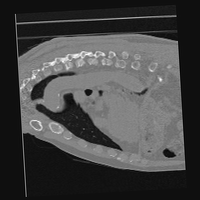

Exp. 3: Adult thorax data: To show the versatility of our approach we also apply it to adult thorax scans. For this experiment no organ specific training is performed but the whole volume is used. We evaluate reconstruction performance similar to Exp. 1 and prediction performance when is projected on an external plane, comparable to X-Ray examination using C-Arms. The latter provides insights about our method’s performance when applied to interventional settings in contrast to motion compensation problems. 60 healthy adult thorax scans were randomly selected, 51 scans used for and nine scans used for . Each scan is intensity normalised and resampled in a volume of with spacing . Using the Fibonacci sampling method, 25 sampling plane of size , evenly spaced between -50 and +50, were rotated over 500 normals. Training took approximately 20 hours for 60 epochs. Fig. 4c shows an example reconstruction result gaining 28dB PSNR with additional SVR. prediction takes approx. 20 ms/slice for this data.

0..5.3 Exp. 3:

We replicated the experiment on adult thorax data without specifically segmented organs. This approach was applied to CT acquisition, shown in Fig 13 and 14, as well as Digitally Reconstructed Radiographs generated using Siddon-Jacobs Ray Tracing shown in Fig. 16.